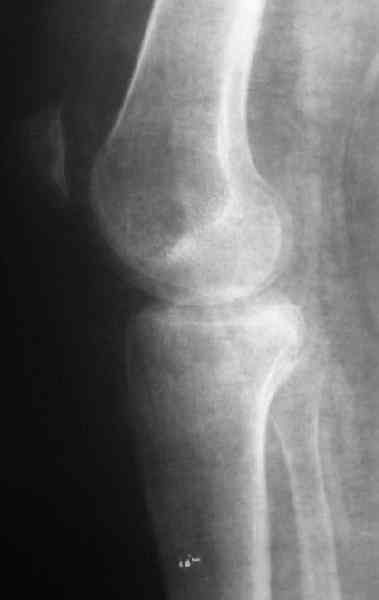

Застарелый перелом 41С3

Обратился больной 46л. 3-месяца назад в каком-то городке Дальнего Востока упал с высоты, сделана Р-графия, наложена гипсовая повязка, от предложенной операции отказался и уехал домой, дальше где и как лечился, не говорит.

Ходит при помощи двух костылей, жалобы на боли при нагрузке, в покое и при движении, без нагрузке боли нет, разгибание 175 гр, сгибание 90 гр, симптомов повреждения связочного аппарата к/с не определяется, от предложенного артродеза пока отказывается.

По тактике лечения, более импонирует второй вариант, но наружная плато расколота и туда при нагрузке внедряется н/мышелка бедра, поэтому после дистракции как репонирвать: или стяжными винтами, или изогнутами спицами или субхондральная костная пластика?

У пациента основной проблемой является импрессионый перелом наружного мыщелка, уже неправильно сросшийся, по-видимому. Аппаратом закрыто можно только подправить угол на уровне метадиафиза. Что

улучшит разве что внешний вид конечности, но не решит основной проблемы - грубой деформации суставной поверхности.